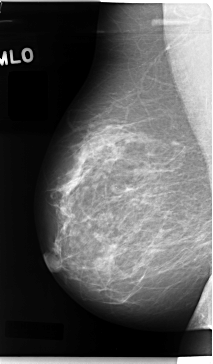

C_0059_1.LEFT_MLO

RIGHT_MLO LINES 4720 PIXELS_PER_LINE 2768 BITS_PER_PIXEL 12 RESOLUTION 50 NON_OVERLAY